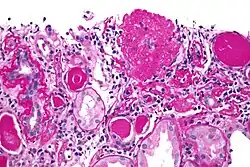

![]() | |

| Light micrograph of focal segmental glomerulosclerosis, hilar variant. Kidney biopsy. PAS stain. | |

On histology, FSGS manifests as scarring (sclerosis) to segments of glomeruli; moreover, only a portion of glomeruli are affected.[7][20][21] The focal and segmental nature of disease seen on histology help to distinguish FSGS from other types of glomerular sclerosis.[21]

Diagnosis of FSGS is made by renal biopsy that includes at least fifteen serial cuts with at least eight glomeruli.[32][33] Histologic features include sclerosis (scarring) of a portion (average: 15%) of the glomerular space, with only a portion of glomeruli manifesting any sclerosis.[33]